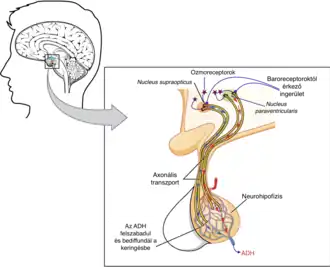

This book chapter explains the role of Vasopressin, also known as antidiuretic hormone (ADH), and the effect it has on motivation. From its role as a hormone regulating the urinary pathway, the physiological role (see Figure 1) is then further explored on the affect vasopressin has on motivation and emotion. Recent research has investigated the role of vasopressin in social behaviour, and key research and theories include:

What is the physiological pathway of vasopressin?

The physiological pathway of vasopressin begins in the hypothalamus (Stevenson & Caldwell, 2015), it then is released into the bloodstream with a relatively short life span before being filtered through the kidneys.This results in vasopressin acting relatively quickly with regulation of body fluid volume (Bankir et al., 2017).

Where is vasopressin made?

The vasopressin hormone originates from the hypothalamus and is stored in the neurohypophysis. Prepropressophysin which includes vasopressin as well as copeptin and neurophysin II are separated in the pituitary and released into the bloodstream in equimolar amounts. The half-life of vasopressin is approximately 3 minutes and is cleared from the blood stream through filtration of the kidneys. As a result, the effects of vasopressin are relatively quick in how it modulates body fluid balance (Bankir et al., 2017).